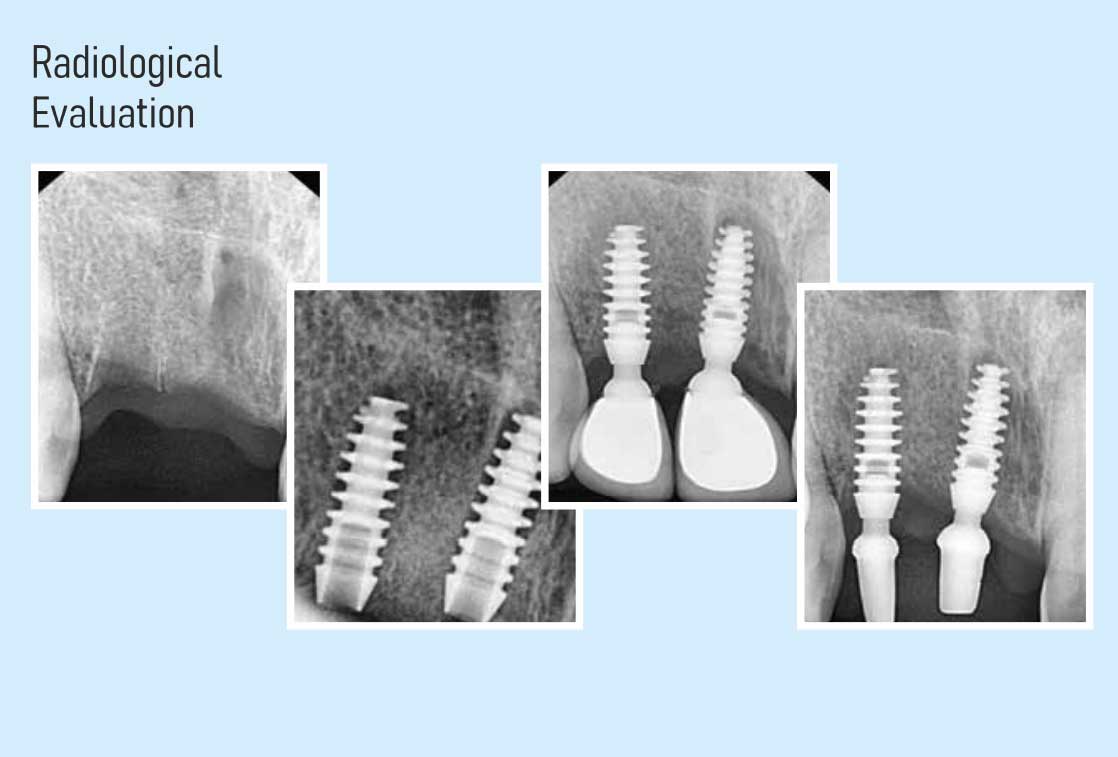

Dental Implant